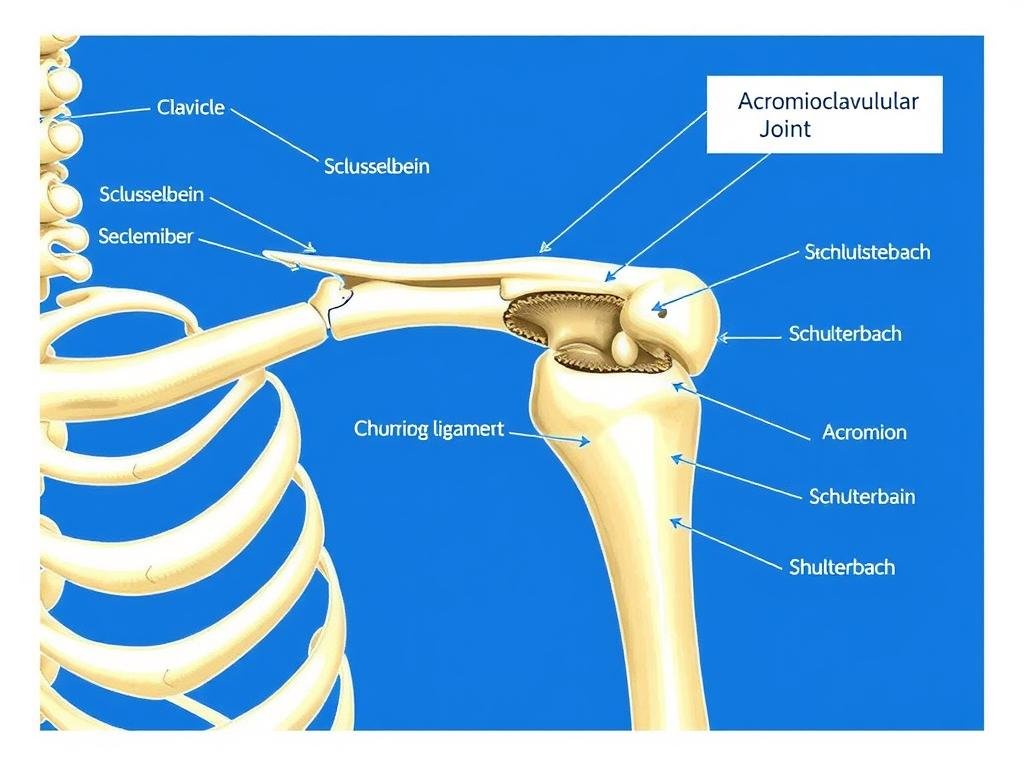

Die inverse (umgekehrte) Schulterprothese unterscheidet sich grundlegend von herkömmlichen Schulterprothesen. Bei einer konventionellen anatomischen Prothese werden die natürlichen Strukturen nachgebildet: Der Oberarmkopf wird durch eine metallische Halbkugel ersetzt und die Gelenkpfanne durch ein Kunststoffinlay.

Bei der inversen Schulterprothese hingegen wird das biomechanische Prinzip umgekehrt:

- Die dem Oberarmkopf ähnliche metallische Halbkugel wird an der Gelenkpfanne des Schulterblatts befestigt

- Die künstliche Pfanne wird am Oberarmkopf angebracht

- Das Drehzentrum des Gelenks verschiebt sich zur Körpermitte und nach unten

- Der Abstand zwischen Oberarmkopf und Schulterdach wird vergrößert

Vergleich: Links eine anatomische Schulterprothese, rechts eine inverse Schulterprothese mit umgekehrter Anordnung der Gelenkpartner.